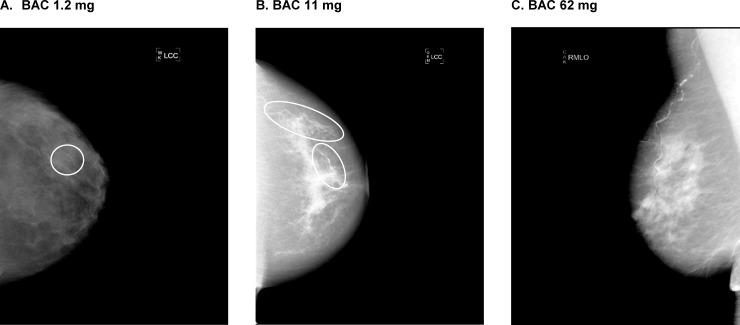

We prospectively enrolled women with no prior cardiovascular disease aged 60 to 79 years undergoing mammography screening at Kaiser Permanente Northern California between 10/24/2012 and 2/13/2015. Urine albumin-to-creatinine ratio (uACR), along with specific laboratory, demographic, and medical data, were measured at the baseline visit. Baseline estimated glomerular filtration rate (eGFR), medication history, and other comorbidities were identified from self-report and/or electronic medical records. BAC presence and gradation (mass) was measured by digital quantification of full-field mammograms.

我们前瞻性地招募了年龄在 60 至 79 岁之间、无既往心血管疾病且在 2012 年 10 月 24 日至 2015 年 2 月 13 日期间在 Kaiser Permanente 北加利福尼亚州进行乳房 X 光筛查的女性。基线检查时测量了尿白蛋白与肌酐比值(uACR)以及特定的实验室、人口统计学和医疗数据。从自我报告和/或电子病历中确定了基线时的估计肾小球滤过率(eGFR)、用药史和其他合并症。通过对全视野乳房 X 光片的数字量化来测量 BAC 的存在和分级(质量)。